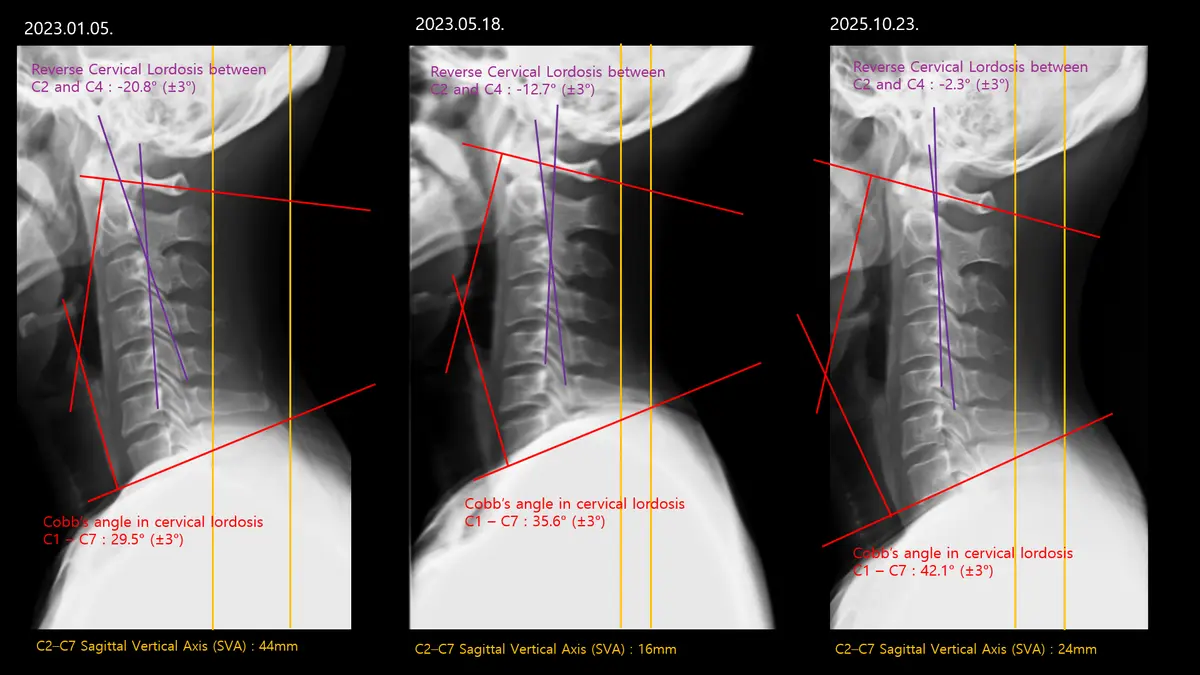

혹시 통증 때문에 운동을 시작했지만, 오히려 더 불편해지거나 나아지지 않는 경험을 해보셨나요? 많은 분들이 근력 부족을 문제로 생각하지만, 사실 통증의 근본 원인은 몸의 '움직임 구조'에 숨어있는 경우가 많습니다. 저희 닥터바디재활운동센터는 동종업계 상위 0.1% 전문가의 정밀한 평가를 통해 고객님 개개인의 고유한 움직임 문제를 정확히 찾아내고, 지속 가능한 변화를 만드는 맞춤형 재활 필라테스를 제공합니다. 저희 센터는 단순한 운동 지도를 넘어, 재활 분야에서 깊이 있는 전문성을 갖춘 책임 교수님과 숙련된 팀원들이 함께합니다. 부산대 물리치료학과 교수, 국가 교육사업 메인강사 등 화려한 경력과 다수의 논문 발표, 실제 현장 노하우로 고객님의 몸을 가장 정확히 분석합니다. '동종업계 상위 0.1% 전문가'라는 자부심으로, 운동의 기초부터 다시 세우는 체계적인 접근을 약속드립니다. 저희 재활 필라테스의 핵심은 '정확한 평가'입니다. 육안으로 확인 어려운 신체 내부 움직임 구조와 불균형을 X-ray 같은 과학적 분석으로 명확히 진단합니다. 척추측만증 Cobb angle이 50도에서 35도로 개선된 사례처럼, 눈에 보이는 변화뿐 아니라 근본적인 신체 구조 회복을 목표로 합니다. 객관적 데이터를 바탕으로 고객님께 가장 필요한 맞춤 솔루션을 제공하여, 통증 없는 건강한 움직임을 되찾아 드립니다. 개개인의 몸 상태에 맞춰 다양한 전문 장비를 활용한 1:1 맞춤 트레이닝을 진행합니다. 레드코드(Redcord) 같은 첨단 슬링 운동 장비로 불안정한 코어 근육을 강화하고, 저항 밴드나 케틀벨로 기능적인 움직임을 회복시키는 훈련을 병행합니다. 단순히 근력을 키우는 것을 넘어, 몸의 협응력과 균형 감각을 향상시켜 일상생활에서의 올바른 자세와 움직임을 자연스럽게 습득하도록 돕습니다. 고객님의 몸이 스스로 최적의 움직임을 찾아갈 수 있도록 섬세하게 설계됩니다. 저희는 고객님 스스로 자신의 몸을 이해하고 관리할 수 있도록 교육에도 힘씁니다. 해부학적 지식, 운동 역학, 다양한 재활 기법에 대한 심도 깊은 강의와 워크숍을 통해 고객님뿐만 아니라 전문가들에게도 올바른 지식을 전달합니다. 이러한 교육적 접근은 고객님께서 운동의 원리를 이해하고, 장기적으로 건강한 생활 습관을 유지하는 데 필수적입니다. 단순히 운동을 시키는 것이 아니라, 몸에 대한 이해를 높여 스스로 건강을 지킬 수 있는 힘을 길러드립니다. 재활 과정은 때로는 힘들고 지칠 수 있습니다. 하지만 저희는 고객님과의 따뜻한 소통과 긍정적인 상호작용을 통해 즐겁고 효과적인 운동 환경을 조성합니다. 고객님의 작은 변화에도 진심으로 공감하고 격려하며, 운동이 단순한 숙제가 아닌 즐거운 일상이 될 수 있도록 돕습니다. '운동의 기초부터 다시 세운다'는 마음으로, 고객님 한 분 한 분의 이야기에 귀 기울이며 최선을 다해 지원합니다. 통증 없는 건강한 삶, 그리고 활기찬 일상은 누구에게나 소중합니다. 저희 닥터바디재활운동센터는 4~12주간의 체계적인 과정을 통해 고객님의 몸이 가진 잠재력을 깨우고, 통증의 악순환을 끊어 지속 가능한 건강을 선물합니다. 이제 더 이상 통증을 참고 운동하지 마세요. 동종업계 상위 0.1% 전문가와 함께, 당신의 몸이 진정으로 원하는 움직임을 찾아보세요. 건강한 변화, 지금 바로 시작하세요!